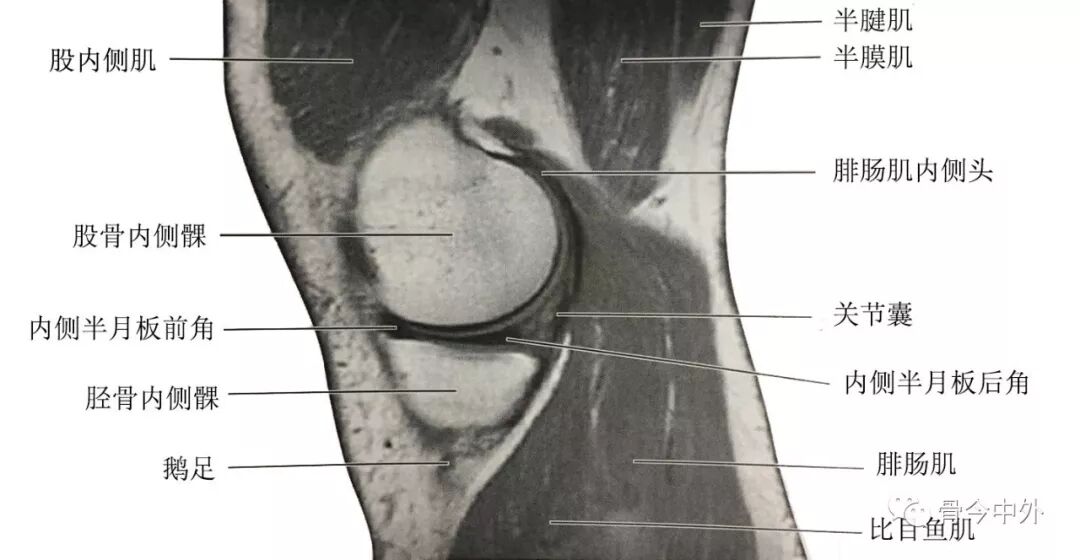

(1)膝内侧部矢状断层:该层面解剖关系结构如图

膝内侧部矢状断层